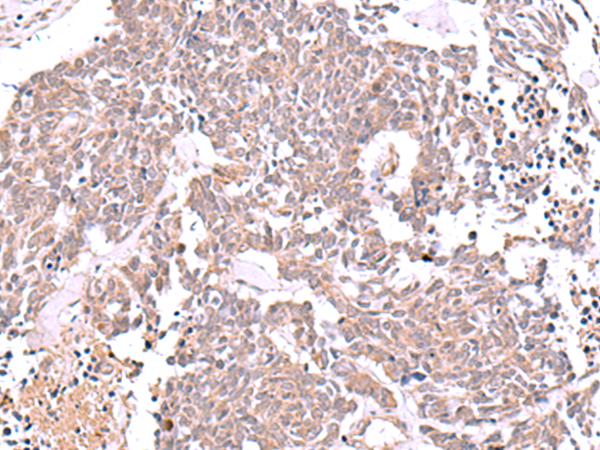

分类: 科研抗体货号: P06768别名: OLC1应用: WB,IHC反应种属: Human, Mouse, Rat